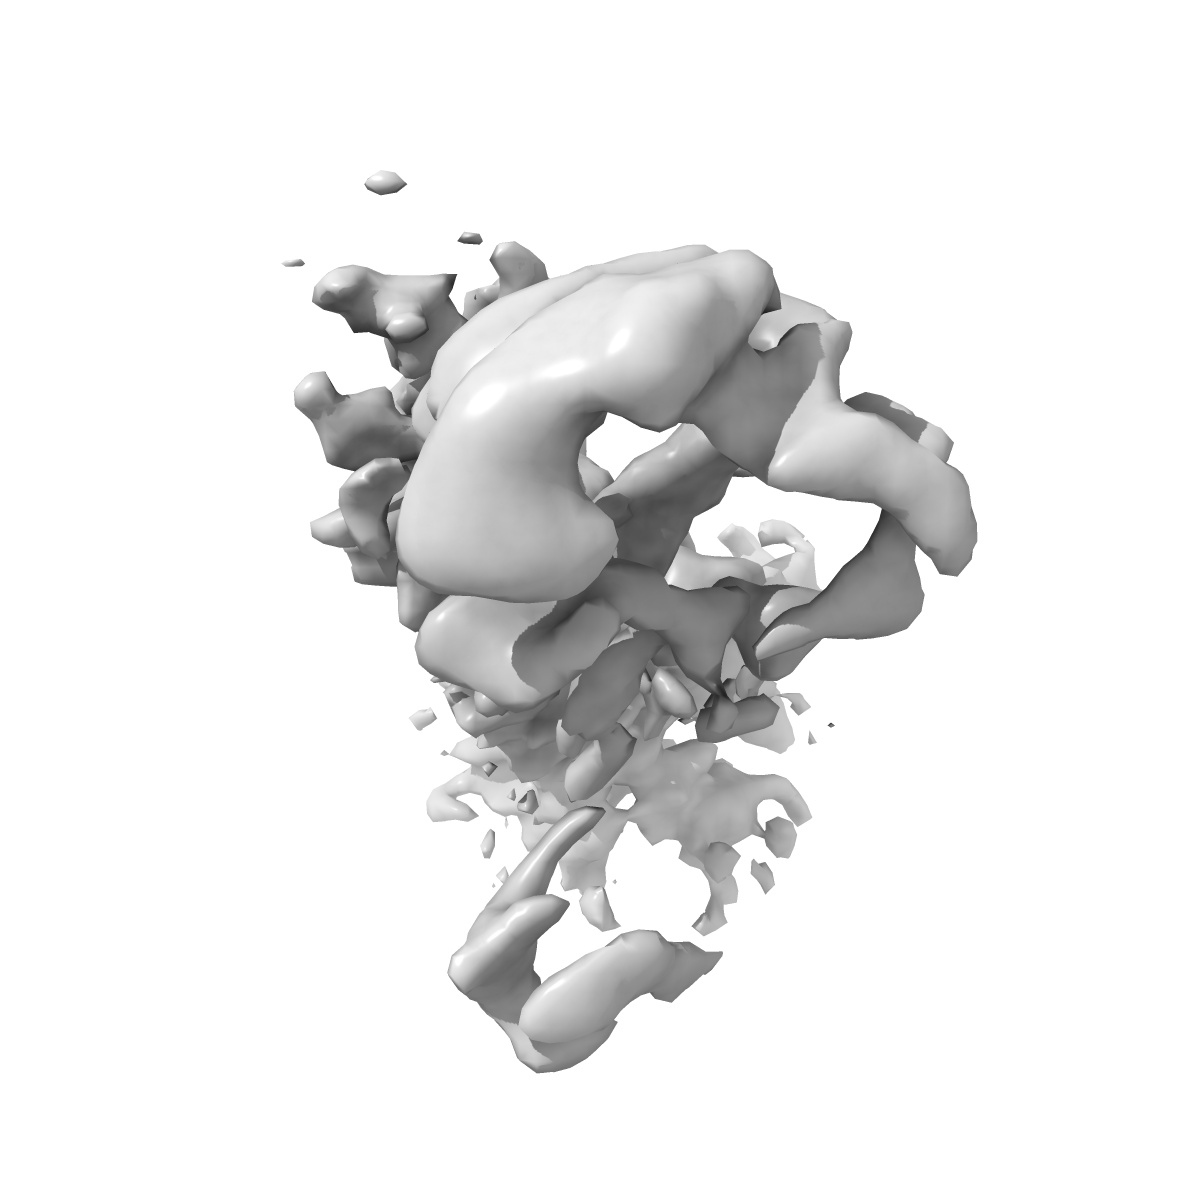

Kappa opioid receptor:Galphai protein in complex with inverse agonist norBNI, Original map receptor

Sample: Kappa opioid receptor in complex with heterotrimeric G protein (Gai/b/g) and inverse agonist norBNI

Structural basis of inverse agonism via inactive kappa opioid receptor:G protein complexes